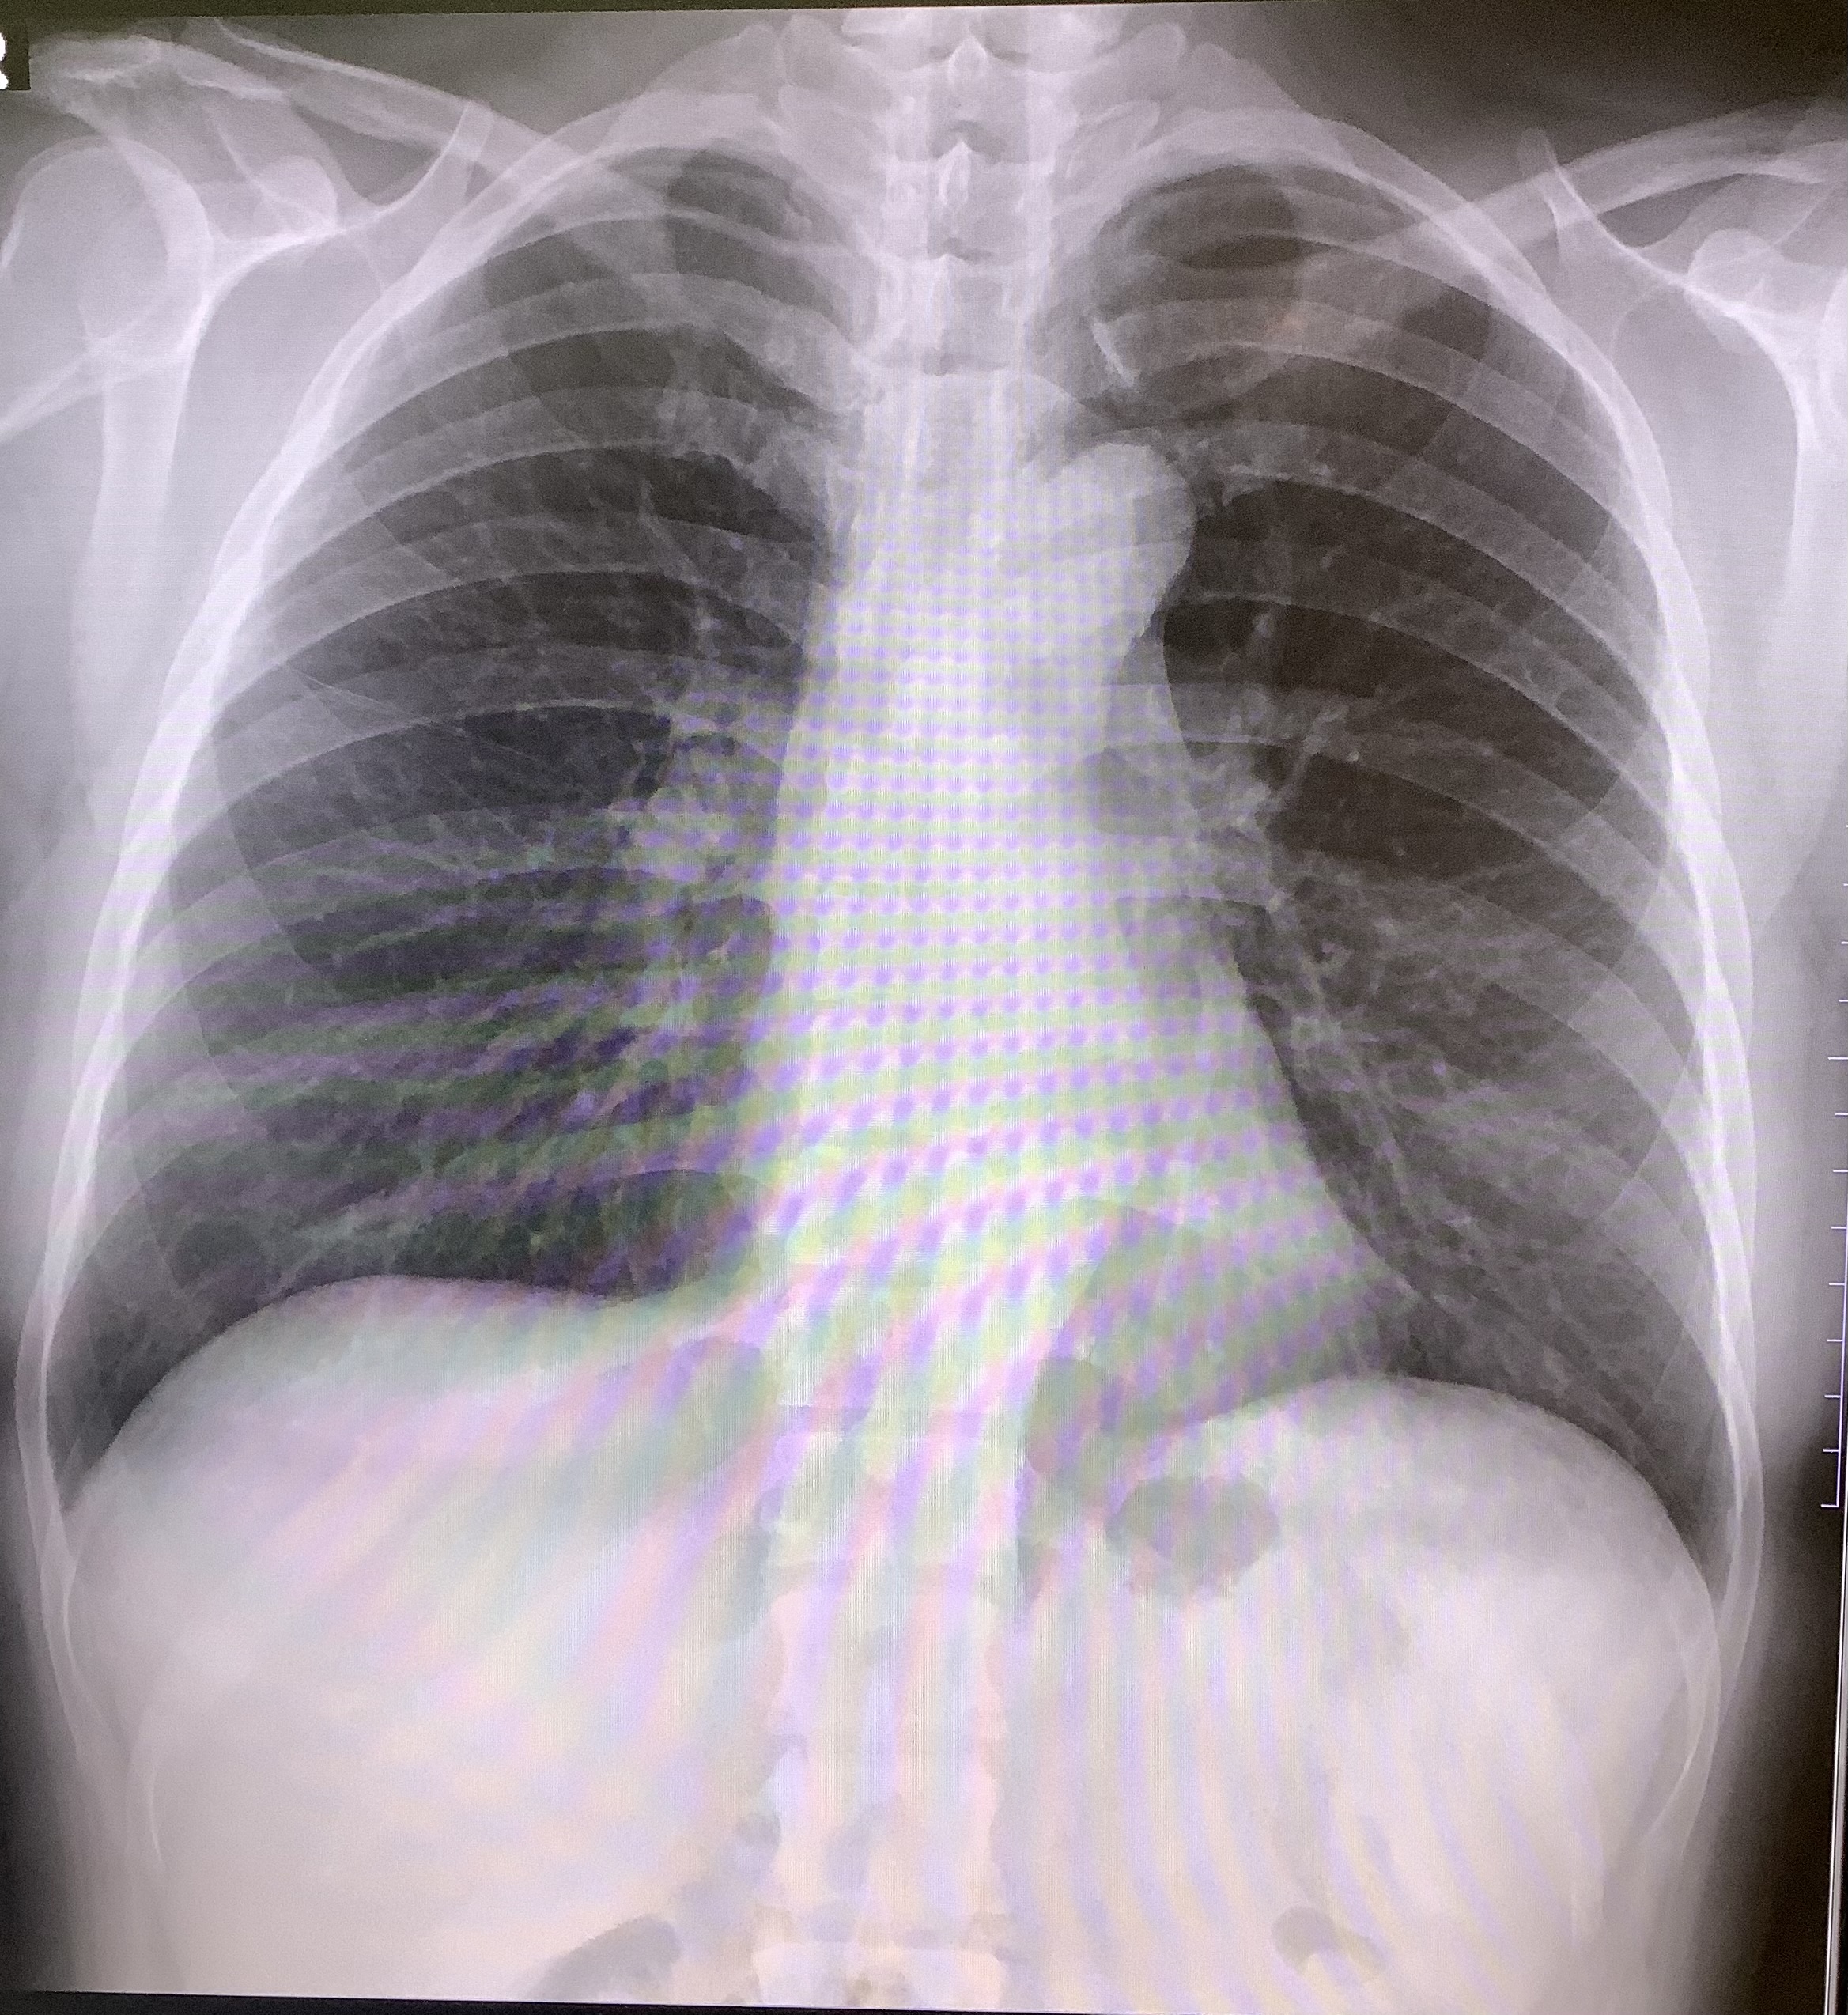

市の胃がん検診、肺がん検診が始まって5か月ほど経ちました。

本院でもまだまだ市の検診、肺がん検診に胃がん検診を受付させていただいております。

また肺がん検診もお気軽に声をかけてくださればスタッフが案内させていただきます